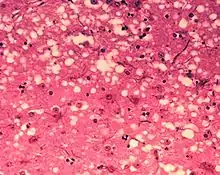

D'un point de vue anatomopathologique, on observe ainsi au niveau de l'encéphale la formation de vacuoles (donnant un aspect spongieux au cerveau, d'où le nom de spongiforme dans EST), une mort des neurones, une gliose (multiplication des astrocytes et de la microglie) et l'accumulation d'une protéine de l'hôte, la PrPC (abréviation de protéine prion cellulaire, l'isoforme normale), sous une conformation anormale (ou mal repliée) alors dénommée PrPSc (abréviation de protéine prion de la scrapie)[6].

- La mise en évidence d'une triade de signes neuropathologiques (perte neuronale, astrogliose, vacuoles spongiformes) ;